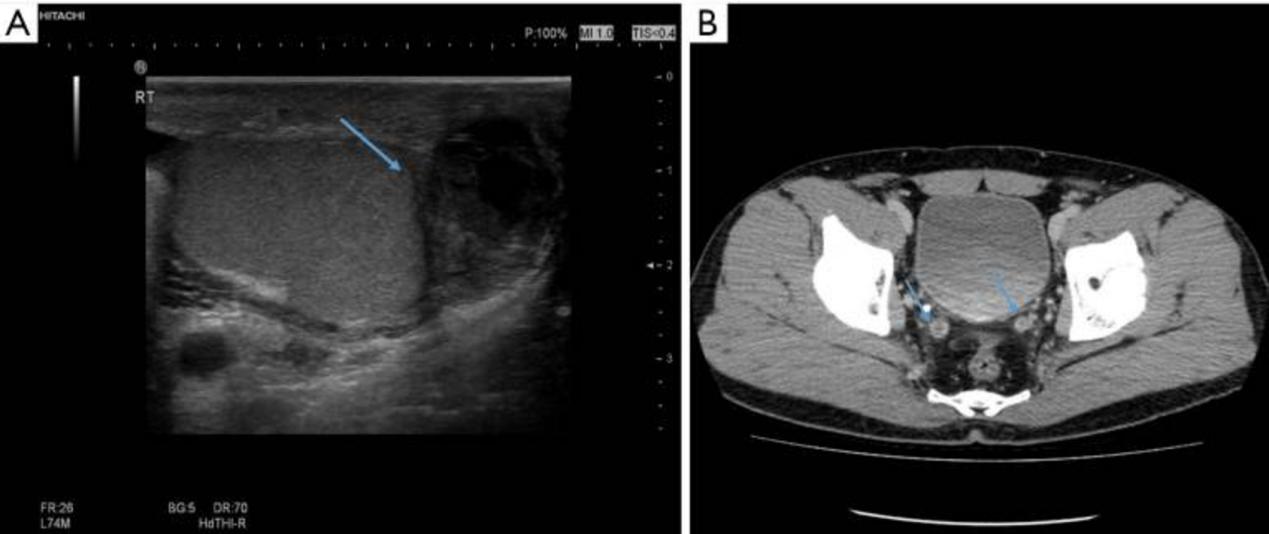

根据组织病理学结果,患者接受吡嗪酰胺治疗3个月,异烟肼和利福平治疗6个月。手术干预后,症状得到缓解,没有任何其他不适。手术后大约1个月,他出现了右睾丸区域的疼痛,尽管疼痛没有之前的左睾丸疼痛那么严重。阴囊超声检查显示右侧附睾区域出现肿胀和不均匀的脓肿(图3)。此外,我们进行了计算机断层扫描(CT)以调查其他器官的受累情况,结果显示在几个淋巴结中发现了可疑的结核淋巴结病。此外,观察到两个输精管增厚,这意味着结核杆菌受累,右侧附睾区域形成脓肿(图3)。考虑到先前诊断为左侧附睾结核,患者被诊断为双侧附睾结核。

图3 术后约1个月进行了阴囊超声检查和计算机断层扫描。(A) 阴囊超声检查显示右侧附睾区(蓝色箭头)出现肿胀和不均匀的脓肿。(B) 在计算机断层扫描上发现两个输精管增厚意味着结核受累(蓝色箭头)